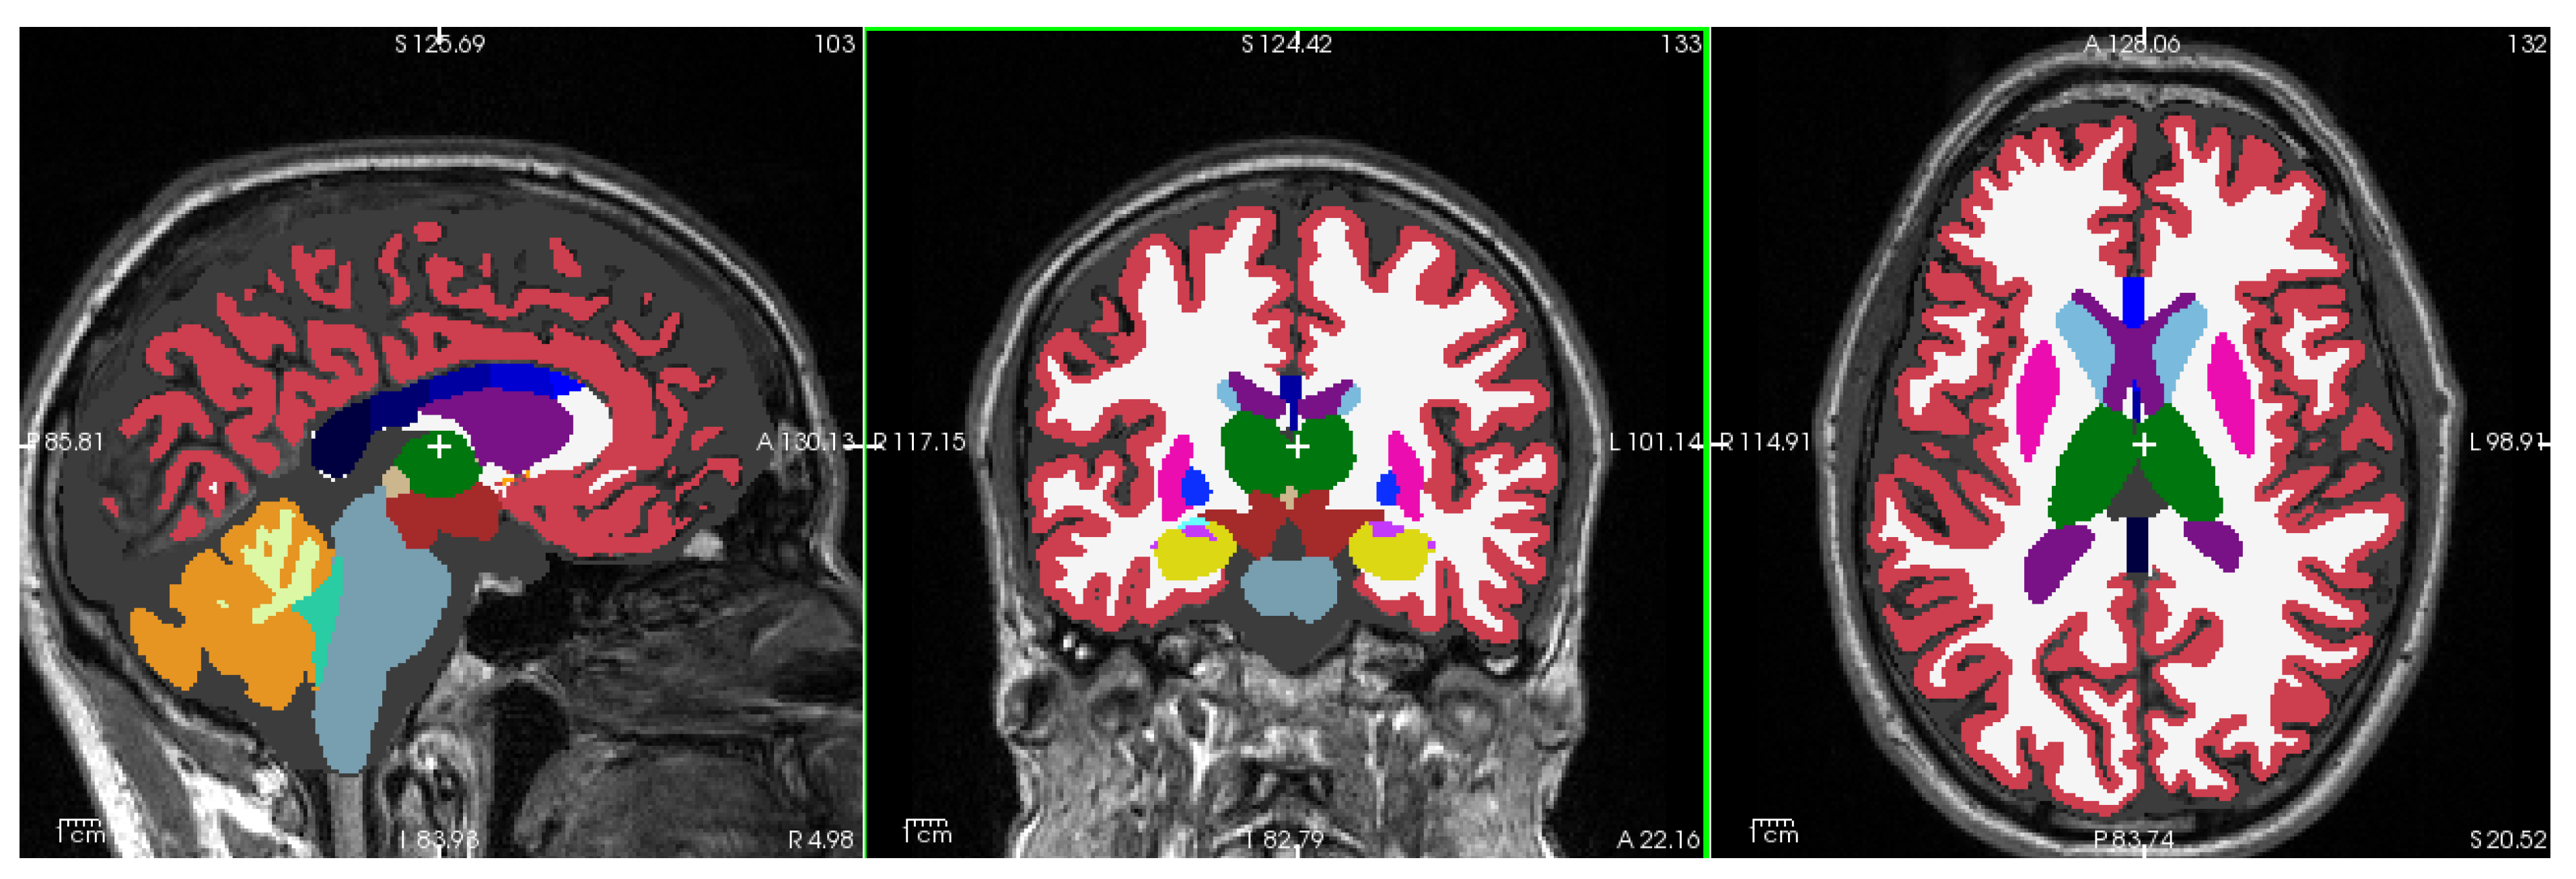

Figure 1 shows a representative T1-weighted image from our dataset, demonstrating the high tissue contrast necessary for accurate morphometric analysis. The corresponding FreeSurfer-generated segmentation mask, which forms the basis for our morphometric measurements, is illustrated in Figure 2. These images exemplify the quality standards maintained throughout our dataset.

Image processing and morphometric analyses were performed using FreeSurfer (https://freesurfer.net), a widely-validated open-source software suite for analyzing brain MRI data [30]. To address both methodological and biological questions, we conducted parallel analyses using two FreeSurfer versions: version 6.0.1, which was employed in the reference study by Skrobisz et al. [23], and the current version 7.4.1.

The evolution of FreeSurfer’s capabilities is particularly relevant to our investigation of brain structure in IBS. Version 7.0 (July 2020) introduced significant improvements in subcortical segmentation accuracy, while version 7.4.1 (June 2023) further enhanced the precision of limbic system structures, notably the hippocampus and amygdala. Additionally, version 7.4.1 provides superior compatibility with multi-modal imaging data and implements refined longitudinal processing algorithms. Since our multimodal MRI examinations were part of a longitudinal IBS intervention study (Berentsen et al. [24]), we also used the longitudinal stream capability of FreeSurfer 7.4.1 to compare baseline longitudinal analysis with a cross-sectional analysis of the first MRI examination.

For both versions, we focused on the automated segmentation of subcortical structures using FreeSurfer’s aseg pipeline, which identifies and quantifies the volume of distinct brain regions (detailed in Table Appendix A.1). This dual-version approach serves two purposes: first, it enables direct comparison with Skrobisz et al.’s [23] findings, and second, it allows us to assess the impact of software evolution on morphometric measurements on a fixed dataset, and differences in cross-sectional and longitudinal stream analysis to discriminate HC and IBS from brain morphometric features. This methodological consideration is crucial, as previous studies have demonstrated that version-dependent variations in automated segmentation can significantly influence morphometric results [31,32,33,34,35,36]. By analyzing our data with both versions, we can distinguish between genuine biological differences and methodologically-induced variations in brain morphometry.

The enhanced accuracy of version 7.4.1 is particularly relevant for our investigation of IBS, as it provides more reliable quantification of brain regions implicated in visceral sensation, pain processing, emotional regulation, and cognitive function.

We will also like to add that in vivo brain segmentation technologies move very fast. Recently (November 2024), the FreeSurfer 8.0.0-beta version enables histological super granularity with identification and volume measurements from more than 300 distinct regions per hemisphere (cf. Figure A2). The aseg mask provides less than 40 brain regions and their volumes within the intracranial space.